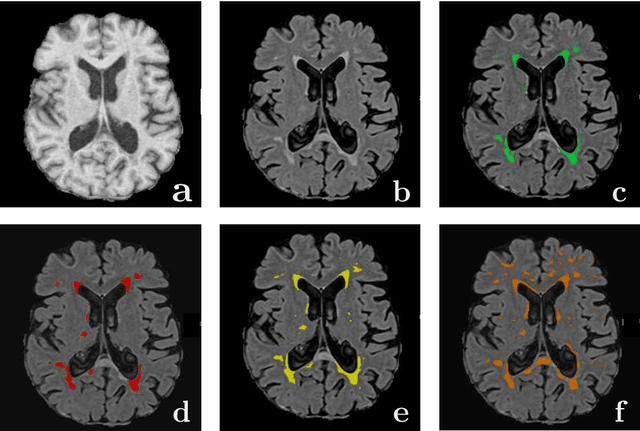

Abstract:Magnetic Resonance Imaging (MRI) is widely used in routine clinical diagnosis and treatment. However, variations in MRI acquisition protocols result in different appearances of normal and diseased tissue in the images. Convolutional neural networks (CNNs), which have shown to be successful in many medical image analysis tasks, are typically sensitive to the variations in imaging protocols. Therefore, in many cases, networks trained on data acquired with one MRI protocol, do not perform satisfactorily on data acquired with different protocols. This limits the use of models trained with large annotated legacy datasets on a new dataset with a different domain which is often a recurring situation in clinical settings. In this study, we aim to answer the following central questions regarding domain adaptation in medical image analysis: Given a fitted legacy model, 1) How much data from the new domain is required for a decent adaptation of the original network?; and, 2) What portion of the pre-trained model parameters should be retrained given a certain number of the new domain training samples? To address these questions, we conducted extensive experiments in white matter hyperintensity segmentation task. We trained a CNN on legacy MR images of brain and evaluated the performance of the domain-adapted network on the same task with images from a different domain. We then compared the performance of the model to the surrogate scenarios where either the same trained network is used or a new network is trained from scratch on the new dataset.The domain-adapted network tuned only by two training examples achieved a Dice score of 0.63 substantially outperforming a similar network trained on the same set of examples from scratch.